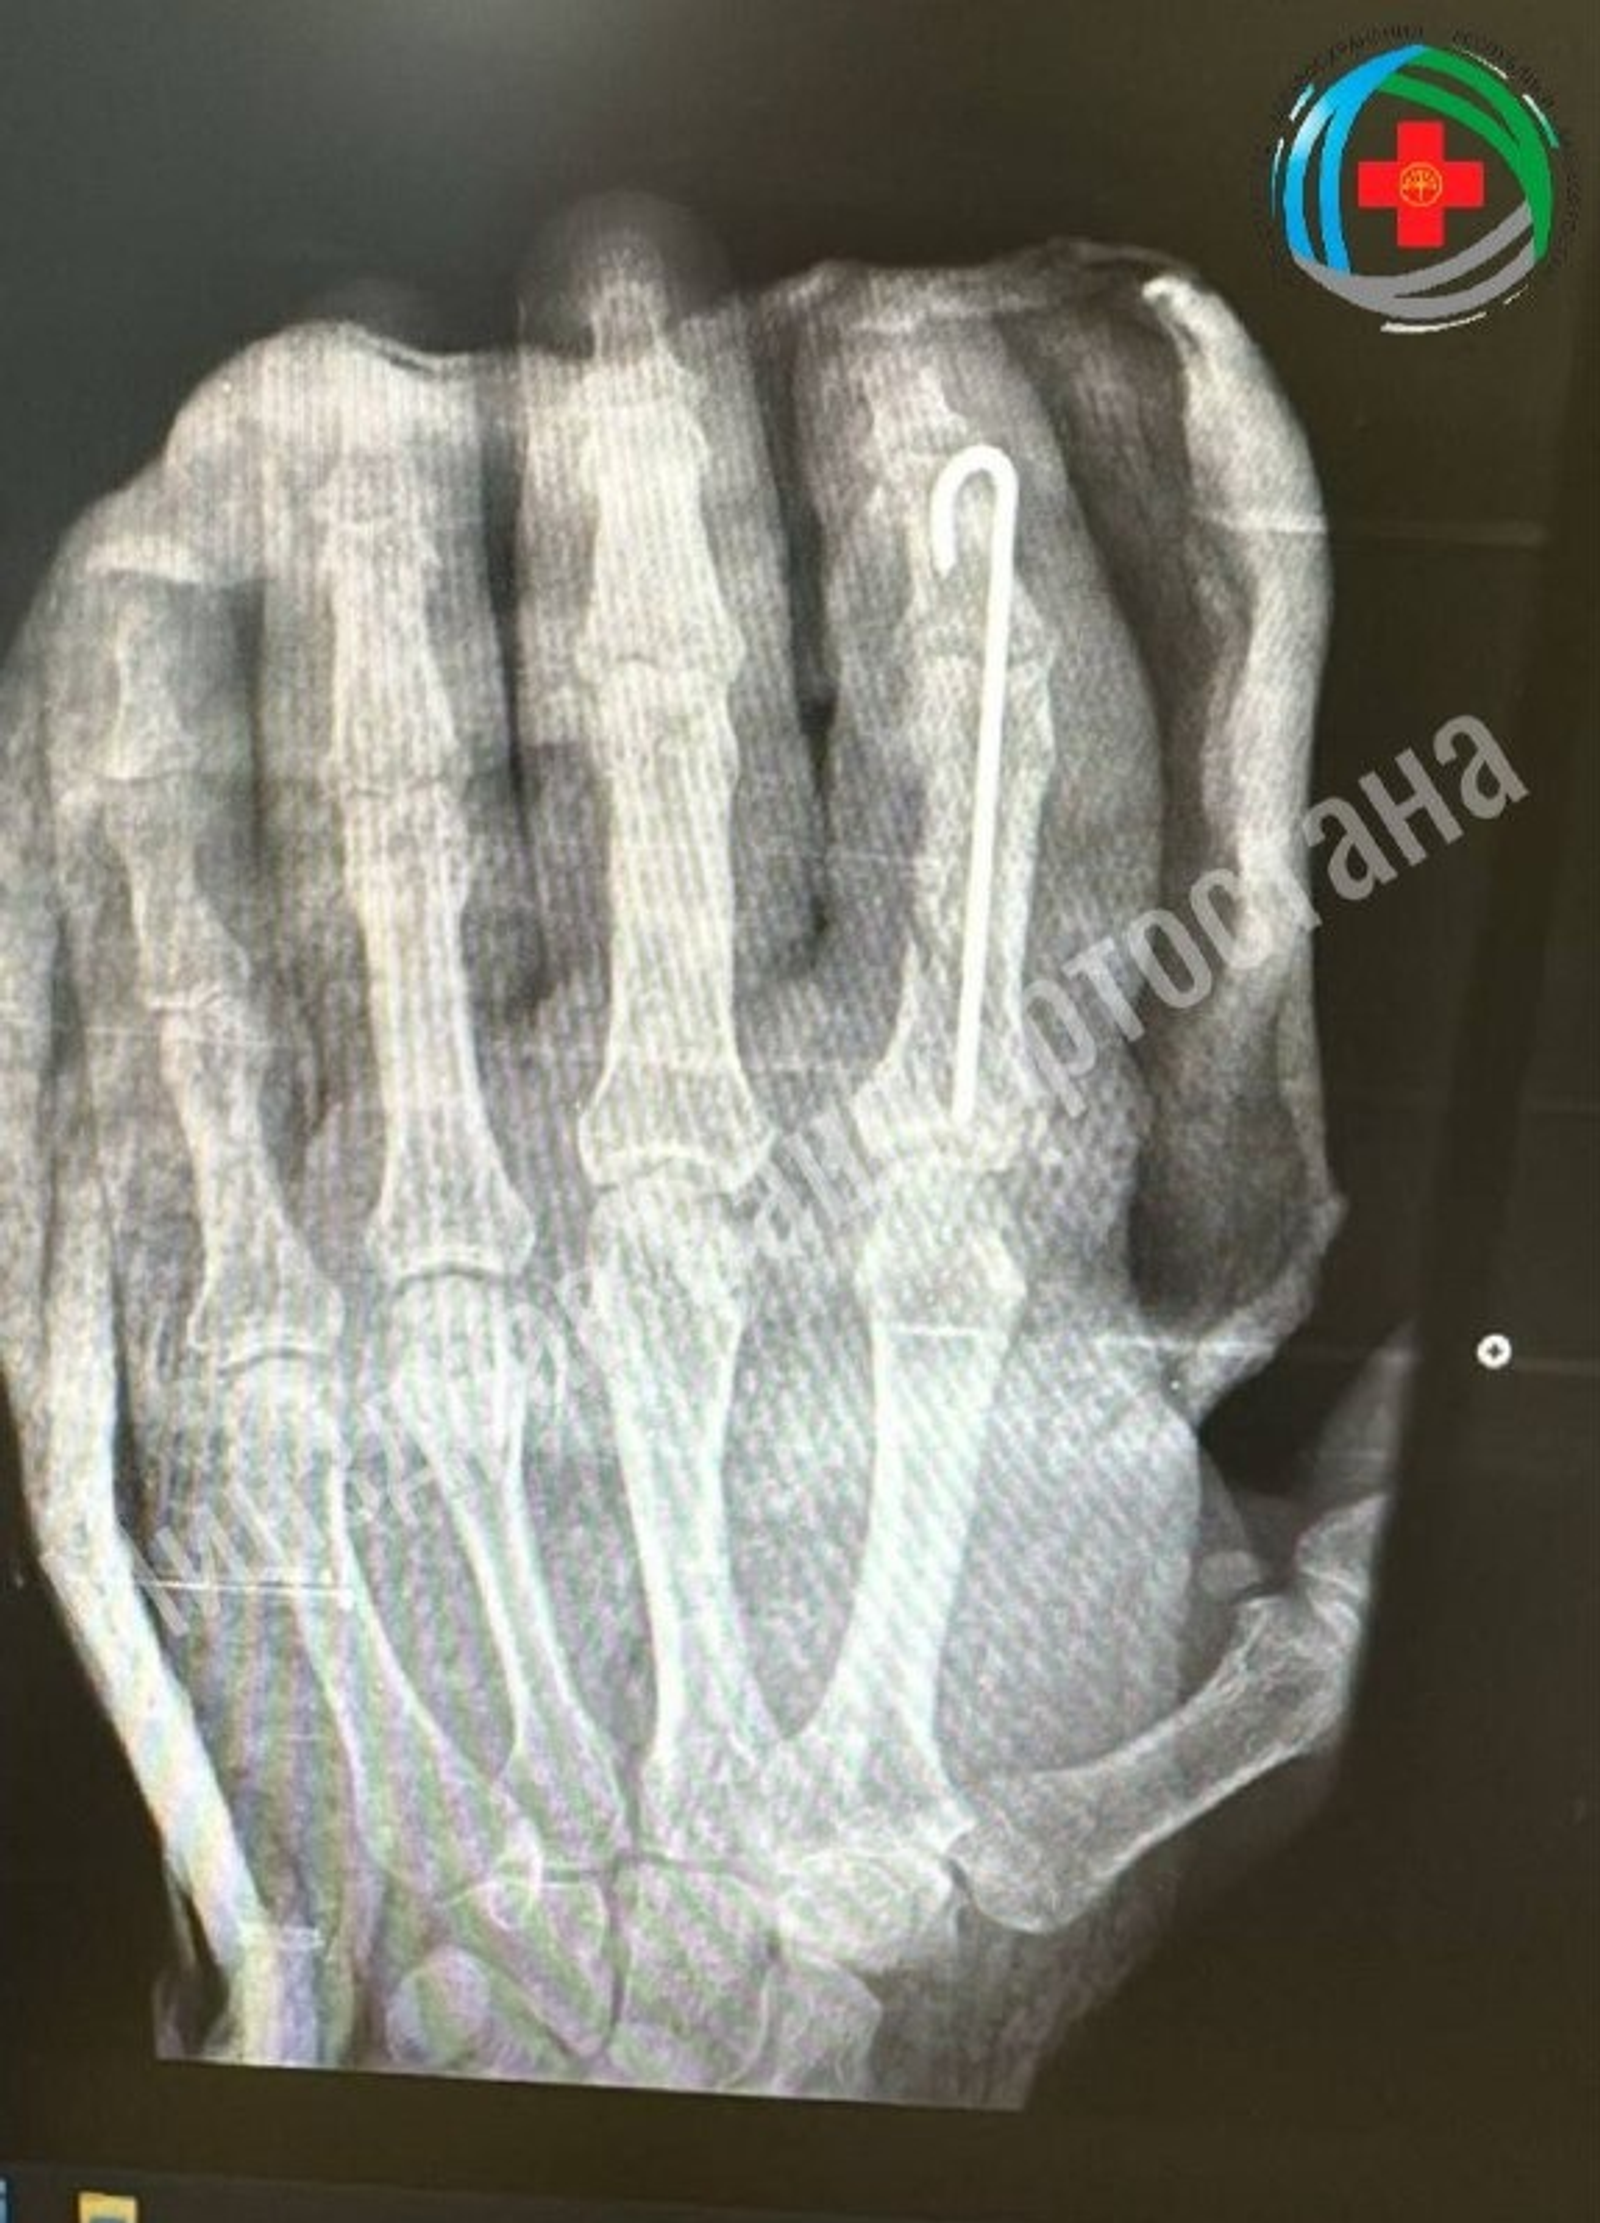

Как сообщили в минздраве республики, мужчина случайно отрубил себе палец руки топором. После осмотра хирурги приняли решение о проведении экстренной операции.

Они провели по-настоящему ювелирную работу: восстановили мельчайшие сосуды для возобновления кровотока, точно зафиксировали кости и реконструировали мягкие ткани, чтобы сохранить полноценное движение пальца.

Орган прижился удачно, мужчина уже может немного пошевелить им. Сейчас он проходит восстановительное лечение, которое включает медикаментозную терапию, физиотерапию и лечебную физкультуру. По результатам лечения ожидается полное восстановление функций пальца.